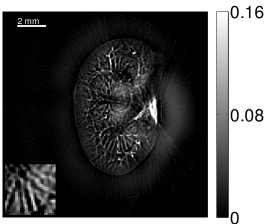

Figure 2(a) shows the image reconstructed by use of the conventional iterative method that utilized a system matrix based on EIR-2. Different values of the regularization parameter from the interval were considered. The reconstructed image with the value of that minimized the RMSE was chosen to represent the best performance of the conventional iterative method. Figure 2(a) and the profile in Figure 2(c) demonstrate that the use of an inaccurate EIR can result in strong artifacts and distortions in images reconstructed by use of the conventional methods.

When the VP algorithm was applied, different values of the regularization parameter from the interval and from the interval were considered. The image that minimized the RMSE was chosen and displayed in Figure 2(b). As revealed by this image and the profiles in 2(c), the VP algorithm yielded an image with fewer artifacts and distortions, and image fidelity was improved as reflected by the reduced RMSE.

The images and EIRs reconstructed by use of the VP algorithm that was based on the 2D imaging model that neglected the SIR are shown in Figures 15 and 16. The latter figure contains results corresponding to different values for the regularization parameter . From Fig. 15, it can be observed that use of the conventional iterative method that utilized the measured EIR resulted in distortions and loss of details in the reconstructed images. Use of the VP algorithm improved the contrast and the details in the reconstructed images (Fig. 15(c) and 16(a)). Furthermore, the images reconstructed by use of the VP algorithm had a more uniform background.

In Figure 17, the results corresponding to use of the 3D imaging model that incorporated SIR effects are shown. The EIR estimated by the VP algorithm is also shown. In Figure 18, images and EIRs reconstructed by use of the VP algorithm with different regularization parameters values are shown.

Similar to the case described above where the transducer SIR was neglected, these results reveal that use of the VP algorithm can produce images with a cleaner background and enhanced spatial resolution than yielded by use of a conventional iterative algorithm that employed the measured EIR. For example, detailed information regarding the vessels near the organ’s periphery was better preserved by the VP algorithm than by the conventional iterative algorithm. These images corroborate our assertion that the VP algorithm can significantly reduce the artifacts and distortions in the reconstructed image. It is also worth pointing out that, unlike the numerical phantom studies, the artifacts and distortions in the images may be caused not only by the inaccurate EIR but also by other factors, such as neglecting acoustic heterogeneities and the variation of the EIRs among the elements of the transducer array. In such cases, the EIR estimated by the VP algorithm represents an effective system impulse response that minimizes the inconsistency between the measured data and the imaging model.